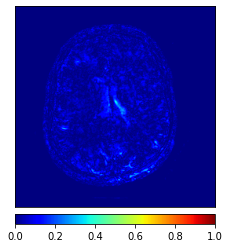

The main limitation of the above-mentioned methods is their dependency on a large number of paired images, i.e., both images belong to the same patient, perfectly registered for training [27], which is difficult to obtain. If the registration has a local mismatch between different modalities, the learning models would generate irrelevant images. To overcome this issue, Zhu et al. [49] proposed cycleGAN to synthesize images from unpaired data in an unsupervised manner. Although cycleGAN has shown remarkable results in reconstructing identical images to the real input, e.g. CT-to-CT, it can not be directly used to synthesize samples from another modality, e.g., MR-to-CT, as there are no direct constraints between real source and synthetic images [39]. For example, Zhang et al. [46] alleviated this issue using an additional loss to force the generated images to be the same as the real ones. Later, SC-cycleGAN [39] defined a structure-consistency loss into the cycleGAN. Specifically, modality-independent neighborhood descriptor (MIND) [9] and a position-based selection strategy is used as structural features and slice selection, respectively. Moreover, several studies conducted bidirectional prediction, i.e., synthesis of CT images from given MR images and vice versa [38, 1]. In addition, many cycleGAN-based methods have been proposed for medical image synthesis from unpaired data [10, 29, 3], but these methods only used the basic discriminator. The basic discriminator only utilizes images in the target domain, while we discovered that using reference images from only the target domain leads to a problem, as shown in Fig. 1 and 2.

In this paper, we propose a bidirectional learning model, known as dual contrast cycleGAN (DC-cycleGAN), for medical image synthesis from unpaired data. Specifically, a dual contrast (DC) loss is formulated that leverages the advantage of samples from the source domain as negative samples to indirectly build constraints between real source and synthetic images via discriminators, and synthesize images more related to the target domain by enforcing the synthetic images to fall far away from the source domain. In addition, structural similarity index (SSIM) [35] and cross-entropy (CE) [48] are integrated into the DC-cycleGAN structure to avoid disappearing gradient information that is caused by a mean absolute error (MAE) and synthesizing irrelevant images. SSIM considers luminance [35] and CE converges fast as its back-propagation error is less than MSE [28]. As can be seen in Figs. 1 and 2, using SSIM and CE with dual contrast can generate more clear and accurate MR images as compared with that of MAE and MSE, and SSIM and CE without dual contrast loss. Although both SSIM and CE with dual contrast and without dual contrast generate similar CT images, SSIM and CE with dual contrast quantitatively generate better images as shown in Table 4. The experimental results indicate that DC-cycleGAN is able to consider more complex features such as structure in synthesizing images and produce remarkable results as compared with other state-of-the-art methods reported in the literature.

Tables 3 and 4 show the results of MR and CT synthesis, respectively. As can be seen, all components play vital role in both tables. SSIM & CE (w) performs significantly better than other losses in synthesizing MR images. This also can be seen visually in Fig. 1. In contrast, SSIM&CE (w) performs slightly better than SSIM&CE (wo) in synthesizing CT images, both generate more or less similar CT images (see Table 4).